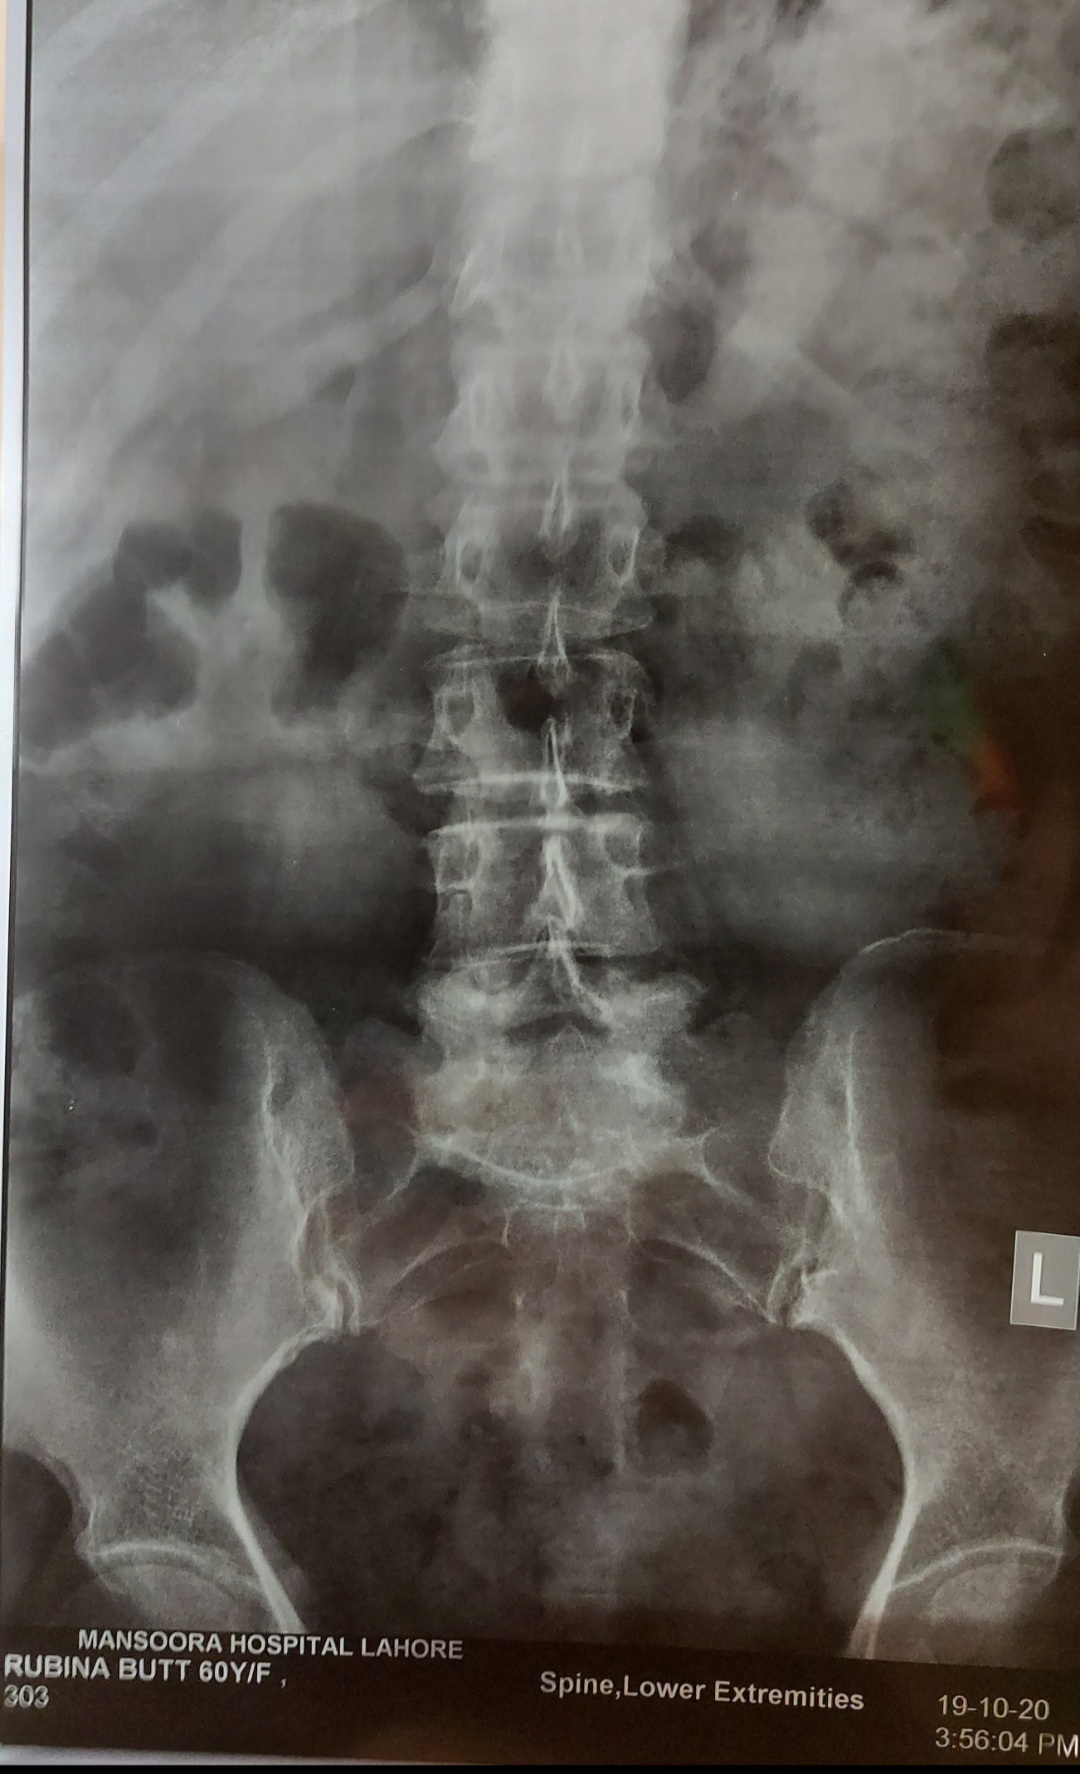

I have pain in my tail bone. Now I have when I sit or stand or lay on bed. Doc said its inflammation HISTORY--> tailbone was injured by falling 2 times at the same spot 5 years ago. I had that similar pain always while sitting or standing for long time but now it has increased n its very painful cant sit in my class. XRAY ATTACHED Thank you in advance